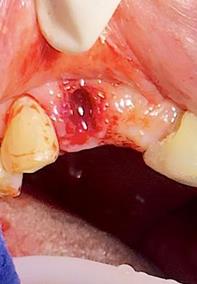

Sindesmotomía con un periostótomo de molt # 9, posteriormente se realizó la luxación con un elevador recto, buscando el punto de apoyo, seguido se efectuó la prensión con el fórceps 150 en el diente con sumo cuidado de no tocar la encía colocándolo hasta el cuello dental, haciendo movimientos de lateralidad y rotación hasta lograr la dilatación del alveolo, y finalmente la tracción del órgano dentario, observando que la raíz este integra, y que estructuras alrededor estén conservadas, de la misma forma se revisó el alveolo en busca de la presencia de granulomas o espículas óseas, una vez ya revisado se procedió al curetaje, con una cucharilla de lucas, se introdujo y se dio paso al retiro del exudado purulento, se realizó irrigación del alveolo con solución fisiológica, una vez limpio se realizó una sutura simple con sutura nylon, seda # 3/0 en el medio del alveolo con la finalidad de aproximar rebordes, evitar su contaminación por el ingreso de comida, además generar una mejor cicatrización en una zona estética , finalmente se aplicó presión por medio de una gasa que mordió el paciente por un lapso de 30 minutos, para contribuir con una hemostasia adecuada.

Figura 8. Irrigación del alveolo con solución fisiológica y sutura simple en la mitad del alveolo.

Elaboración: Los autores.

Finalmente se prescribió al paciente ibuprofeno de 600 mg por cuatro días, se le manifestó instrucciones postoperatorias y control para remoción de puntos en una semana.